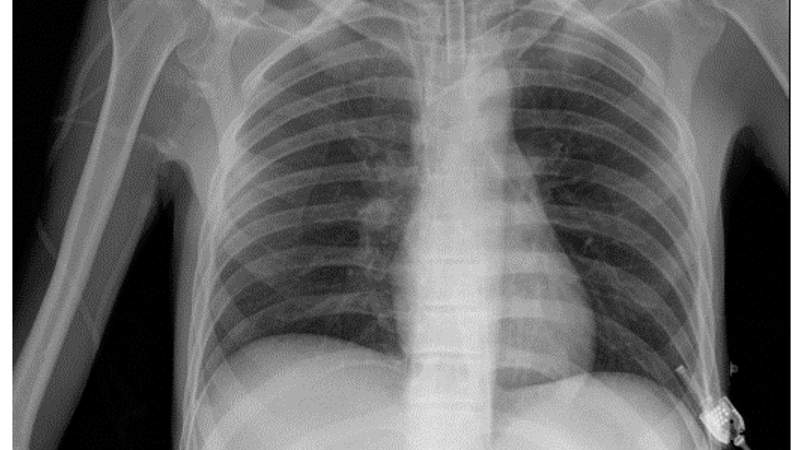

Kết quả hình ảnh X quang ngực bình thường dựa trên các đặc điểm dưới đây:

Xương lồng ngực

Xương ức và xương cột sống ngực có thể không thấy được trên phim thẳng và thấy rõ trên phim nghiêng.

Xương sườn

Nhu mô phổi và rốn phổi

Hai phế trường màu đen ở trên phim chụp chính là hình sáng.

Rốn phổi màu trắng được gọi là hình mờ. Nó xuất phát từ hai bên của bờ tim và có hình rễ cây. Động mạch phổi và các phế quản đã tạo thành rốn phổi. Rốn phổi trái cao hơn rốn phổi phải khoảng 1 - 2 cm. Rốn phổi đã chia nhánh nhỏ dần ra ngoại vi thành của vân phổi. Khi cách thành ngực khoảng 1cm, vân phổi sẽ không còn thấy rõ.

Bóng tim và trung thất

Nằm ở vị trí lệch trái và có đường kính ngang nhỏ hơn ½ đường kính ngang của lồng ngực.

Khí quản và phế quản gốc